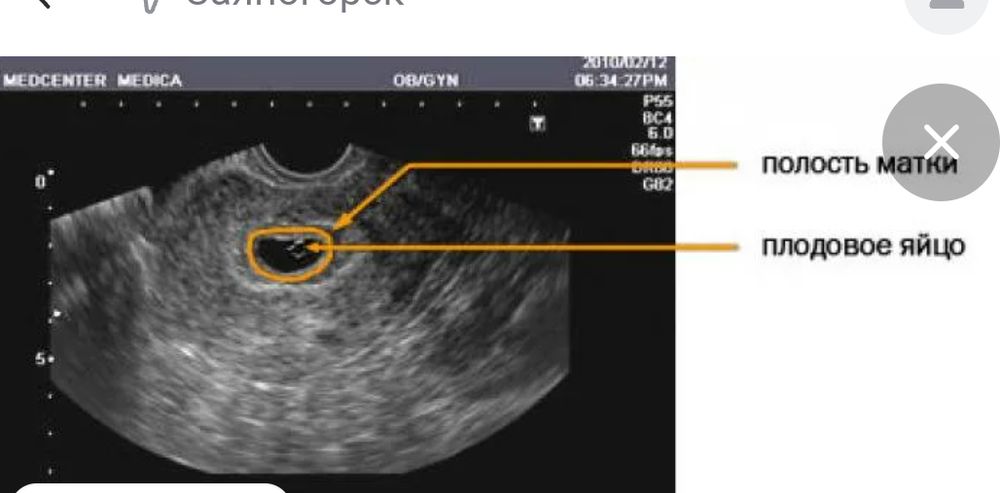

У меня срок 5-6 недель. На УЗИ овальная полость чёрная и внутри светлым контуром шарит -ПЯ.

Свет в окошке, вот так Изображение